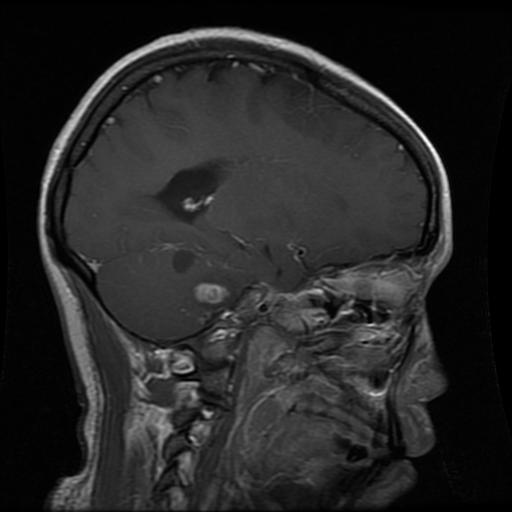

Figure 2: Samples of Meningioma segmentation across different imaging planes

Meningioma: Meningiomas arise from the meninges and are generally well‑circumscribed and homogeneous, making them easier to segment. However, their location adjacent to critical structures such as dural sinuses and cranial nerves can complicate diagnostic tasks. An example of a meningioma and its segmentation mask is presented in Figure 2, illustrating the clarity of its boundaries.